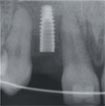

安卓健临床案例分享

安卓健种植产品销往全球100多个国家精密工程CFDA

权威认证,可放心使用。安卓健种植体手术程序简单,

更少创伤,更快恢复,更加安心。